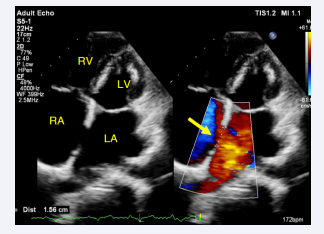

The anterior rim is 8 to 9 mm thick, the posterior rim is 18 mm thick, the distal rim is 17 mm thick, and the proximal rim is 17 mm thick. TEE, showed markedly dilated left atrium (LA). There is a fenestrated defect at the mid IAS with two left-to-right flow jets, the larger of which is 8 mm x 8 mm and the smaller of which is 5 mm x 8 mm, separated by a thin membrane (Figure 5).

Three-dimensional TEE, Mid-esophageal level, 4-chamber  view (20o), demonstrates the large fenestrated ASD Secundum type.

Figure 5: Three-dimensional TEE, Mid-esophageal level, 4-chamber view (20o), demonstrates the large fenestrated ASD Secundum type.

The total defect diameter was 15 mm x 8 mm, the rim thickness was 19 mm proximally and distally, the anterior rim was 8 mm thick, the posterior rim was 13 mm thick, and the superior and inferior rims were 12 mm and 14 mm thick, respectively. The ASD looks like Swiss cheese at 1 O’clock and a band in the middle, and it measures 8 x 8 mm and 8 x 5 mm, about 15 to 16 mm in diameter. She has significant RV dilatation and RA dilatation, with a Qp/Qs ratio of 3.0.